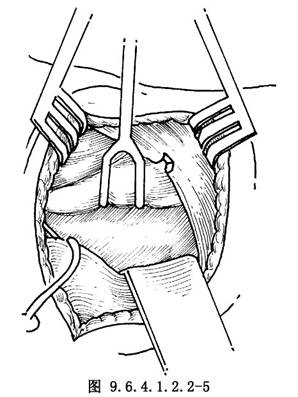

9.4 4.暴露環杓後肌

用小拉鉤牽拉甲狀軟骨翼後緣向上,暴露嚥下縮肌的斜行纖維(圖9.6.4.1.2.2-5)。在接近甲狀軟骨下角處將嚥下縮肌纖維鈍性分開,不要切斷肌纖維,露出梨狀窩黏膜反折處(圖9.6.4.1.2.2-6)。將梨狀窩黏膜向上分離使露出環杓後肌。環杓後肌肌纖維走行與嚥下縮肌肌纖維走行呈垂直關係,此特徵有助於確定環杓後肌。